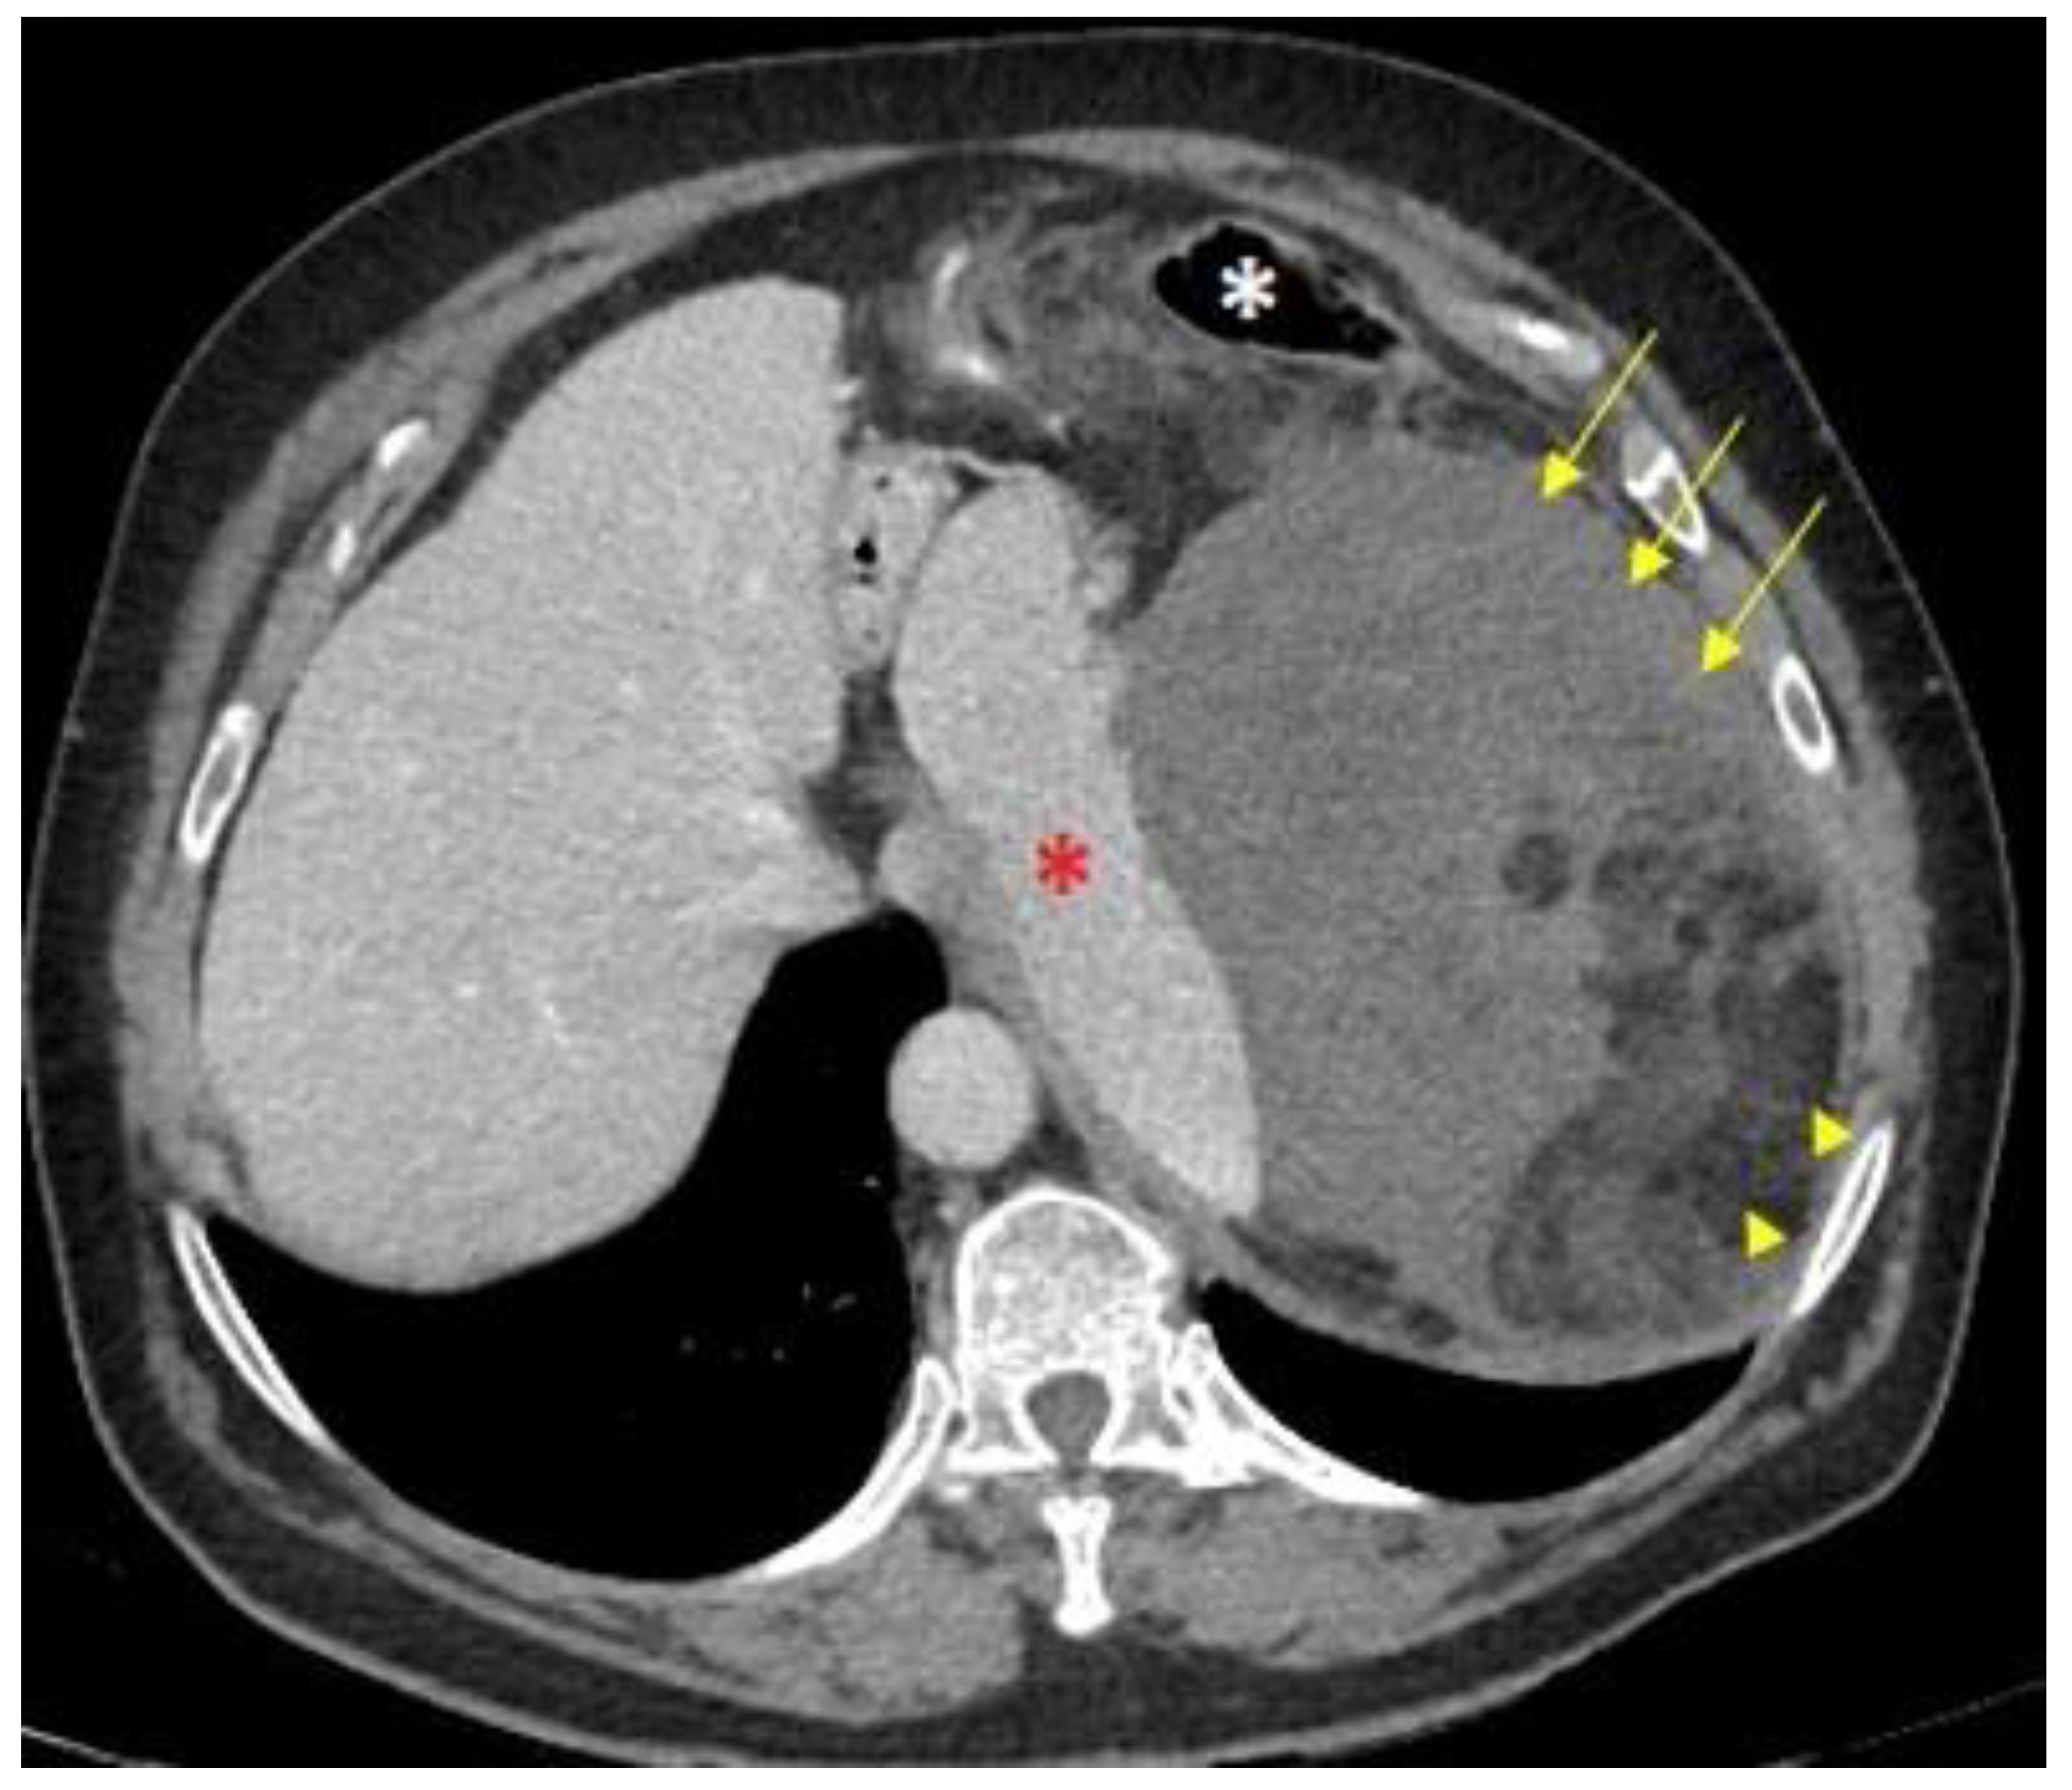

4.1. Imaging Diagnosis

- A CT scan is the imaging technique of choice for the diagnosis and evaluation of resection of retroperitoneal sarcomas (IV, A).

- MRI is also recommended to evaluate pelvic tumors (IV, A).